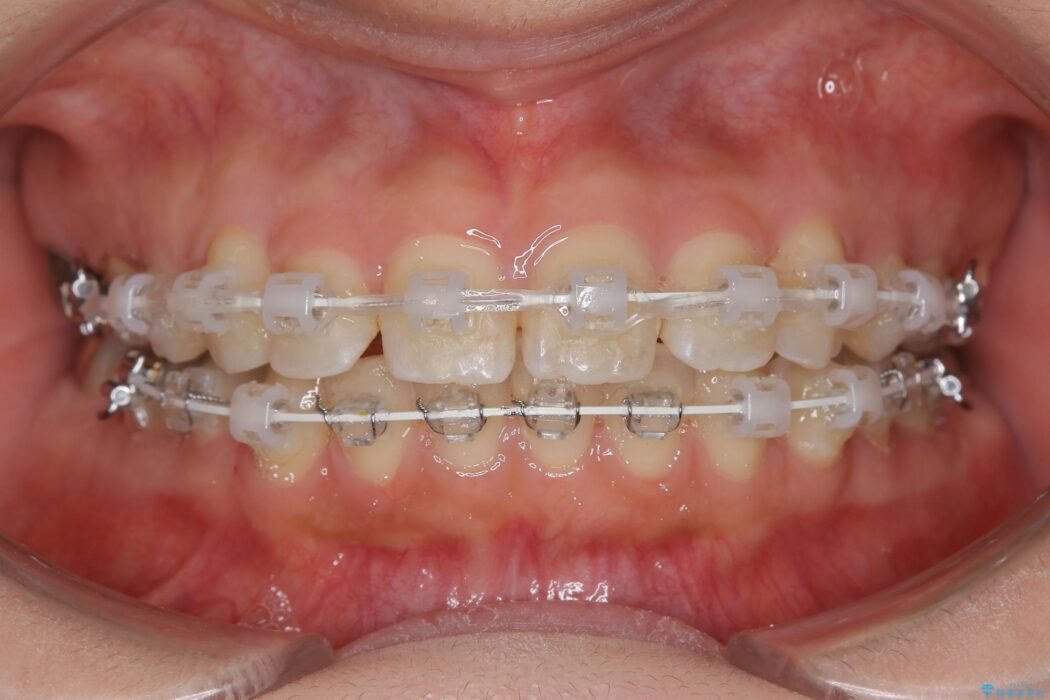

いつもでしたらマウスピース矯正をおすすめするのですが、自己管理の煩わしさから、目立たないワイヤー装置にて矯正治療を行うこととしました。

後戻りの程度としては軽度なので、治療期間としては短く終えることが出来ました。

前歯の正中線も改善され大変満足していただきました。